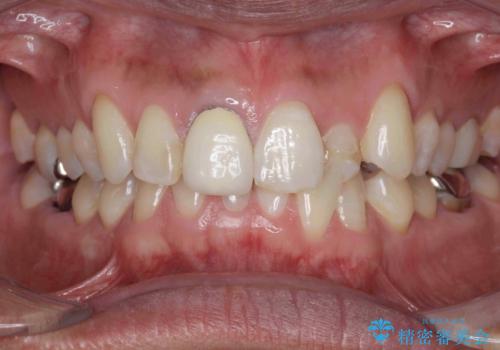

- 奥に引っ込んでいる前歯を矯正治療で並べたい!色の気になる前歯のクラウンをやり替えたい!と希望され来院されました。

奥に位置している前歯を部分ワイヤー矯正ののちマウスピース矯正インビザラインで並べ、矯正治療後に審美的なジルコニアクラウンを作製していきます。